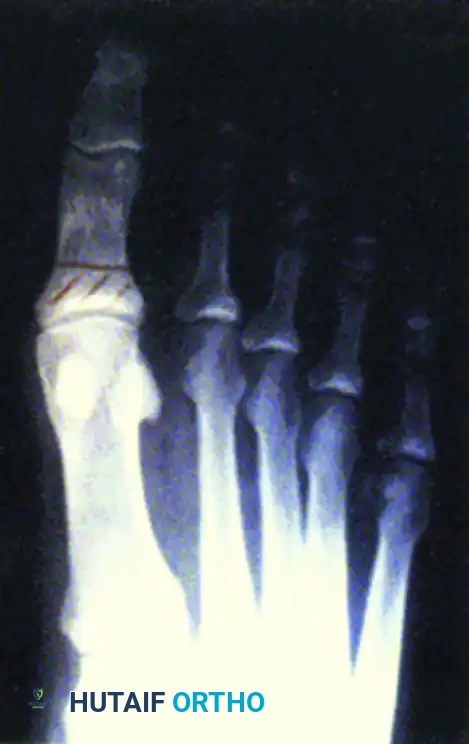

Type 5: Forefoot

- Prevalence: A rare form of true Charcot arthropathy, though neuropathic forefoot complications are common.

- Pathoanatomy: Dislocation of the metatarsophalangeal (MTP) joints leads to severe claw toe deformities, retrograde buckling of the metatarsal heads, and subsequent plantar ulcerations.

- Clinical Correlation: Grade 3 ulcers under the metatarsal heads (e.g., the second metatarsal) frequently extend directly into the bone, resulting in contiguous osteomyelitis that requires aggressive debridement or ray resection.